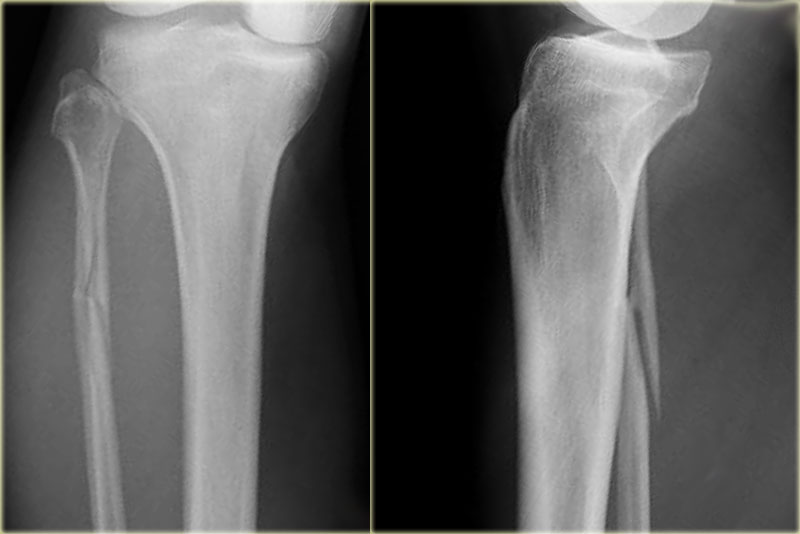

PE stage 3 PE stage 3

Additional radiographs of the lower extremity were ordered and they demonstrate a high fibular fracture, i.e. Weber C stage 3 also known as a Maisonneuve fracture.